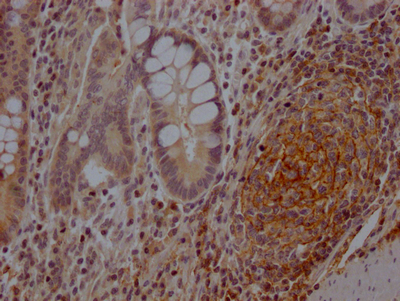

IHC image of CSB-RA978310A0HU diluted at 1:100 and staining in paraffin-embedded human endometrial cancer performed on a Leica BondTM system. After dewaxing and hydration, antigen retrieval was mediated by high pressure in a citrate buffer (pH 6.0). Section was blocked with 10% normal goat serum 30min at RT. Then primary antibody (1% BSA) was incubated at 4℃ overnight. The primary is detected by a Goat anti-rabbit IgG polymer labeled by HRP and visualized using 0.05% DAB.